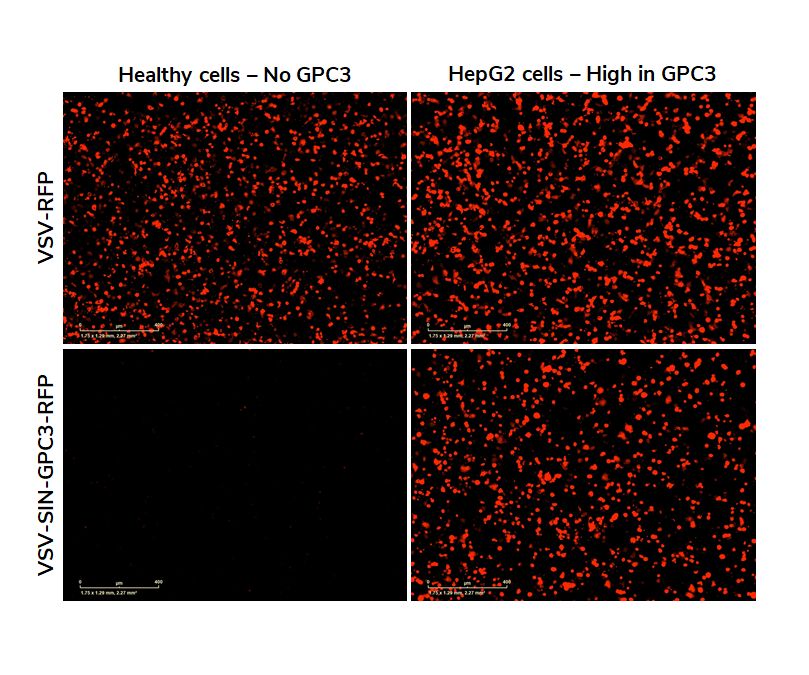

Here we show the results of an infection test. We compare the selectivity of wild-type VSV with an engineered version of VSV targeting GPC3. The red dots are fluorescent proteins indicating infection of cells. It is clear that VSV wild-type infects both the healthy and the HepG2 cancer cells. The retargeted VSV only infects the HepG2 cells.